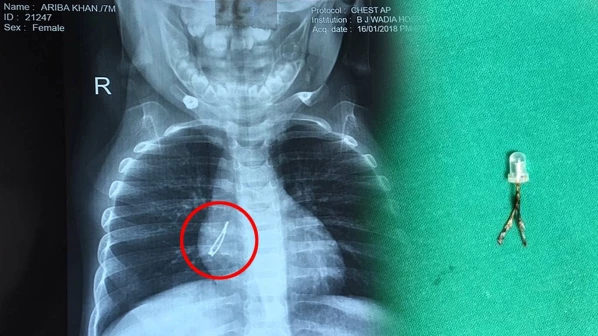

७ महिन्यांच्या अरिबाने गिळला एलईडी बल्ब!

Jan 25, 1:04 AM IST